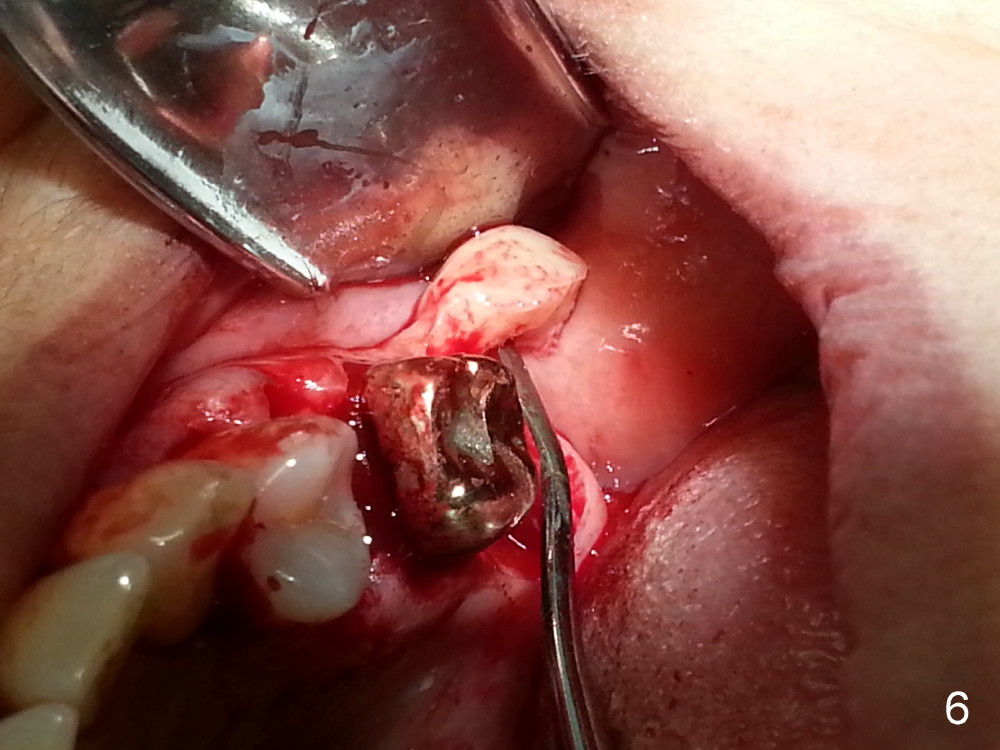

The tooth #13 appears to be affected by periodontits and occlusal trauma (Fig.1*). After using a periotome (Fig.2), the tooth is extracted (Fig.3). The buccal flap is raised (Fig.4). Gingival graft is to be harvested from the site of #15 (Fig.5). The tissue is elevated buccally (Fig.6) and separated (Fig.7). The donor site is covered by a collagen membrane (Fig.8*). A diamond bur is used to induce bleeding from the socket (Fig.9*). Osteotomy is initiated (Fig.10) and enlarged (Fig.11,12). A tapered implant is being placed (Fig.13-15) following internal sinus lift (Fig.16,17). The implant is placed subcrestally, followed by bone graft (Fig.18), soft tissue graft (Fig.19), and suturing (Fig.20 <, Fig.21).